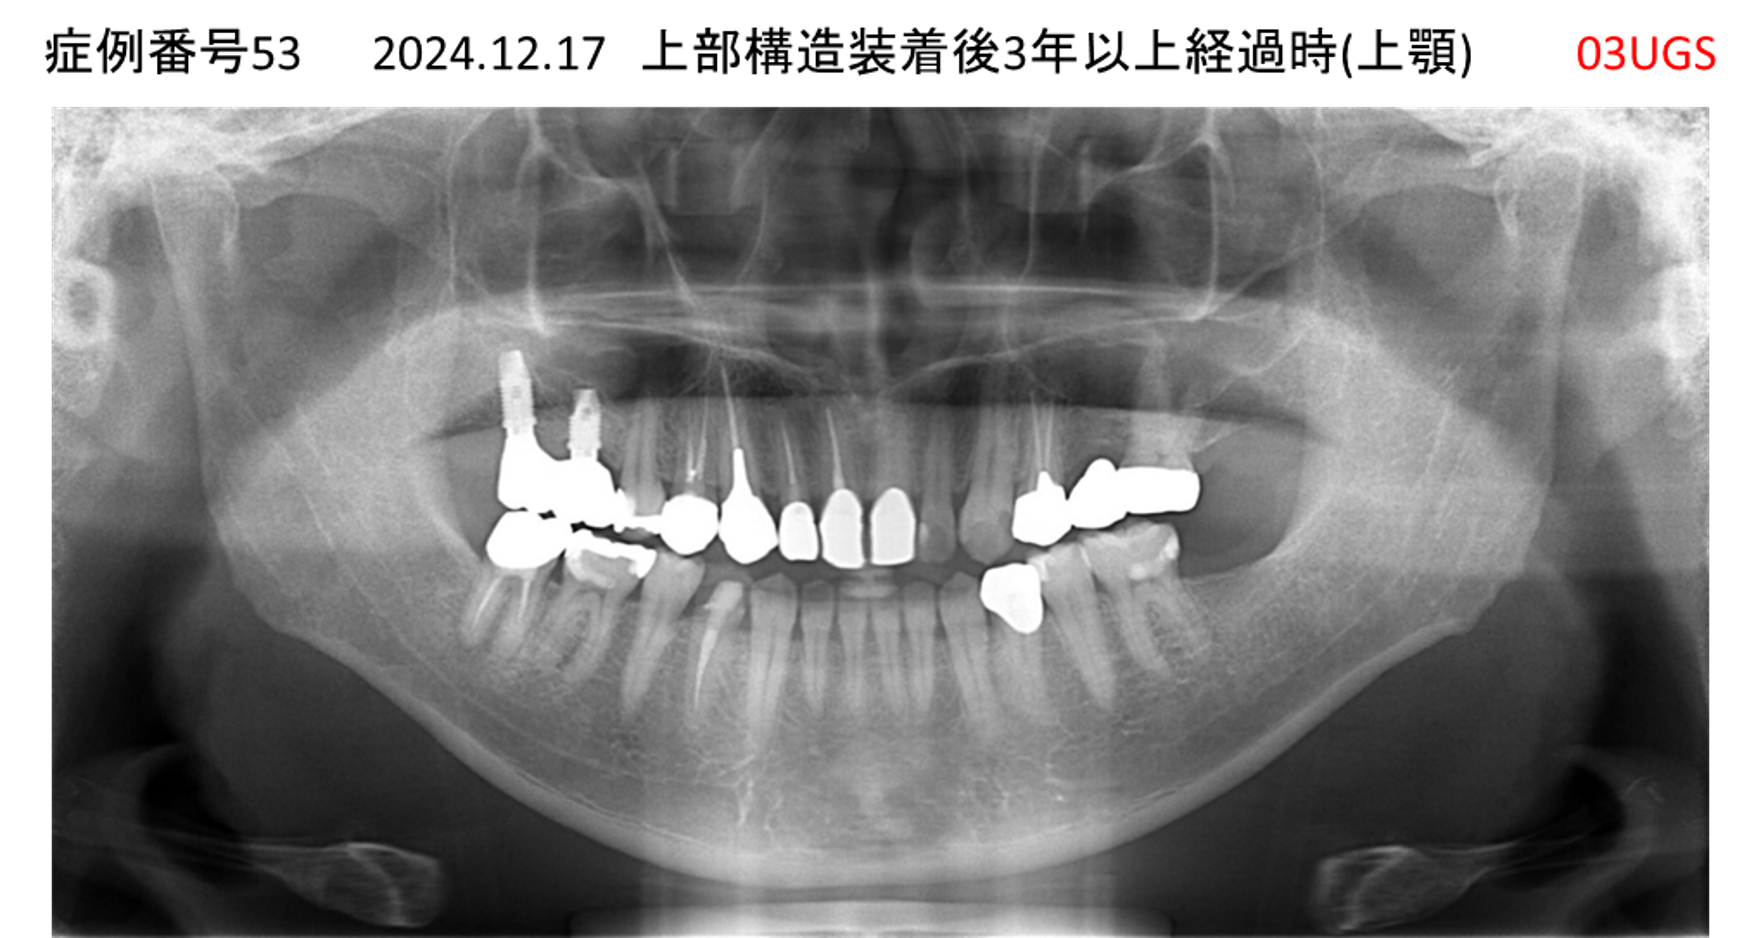

かめない/上の歯が揺れてきた患者様のインプラント症例

| 治療名称 |

インプラント |

| 治療費用 |

390万円+税 |

| 治療期間 |

6か月 |

| 患者さんの症状(主訴) |

かめない。上の歯が揺れてきた。 |

| 治療内容 |

サイナスリフト、抜歯即時インプラント |

| 治療結果 |

上の歯の揺れが収まった。噛めるようになった。食事がおいしい。 |

| 治療の注意点(リスク/副作用) |

インプラントが壊れたら再治療が必要 |